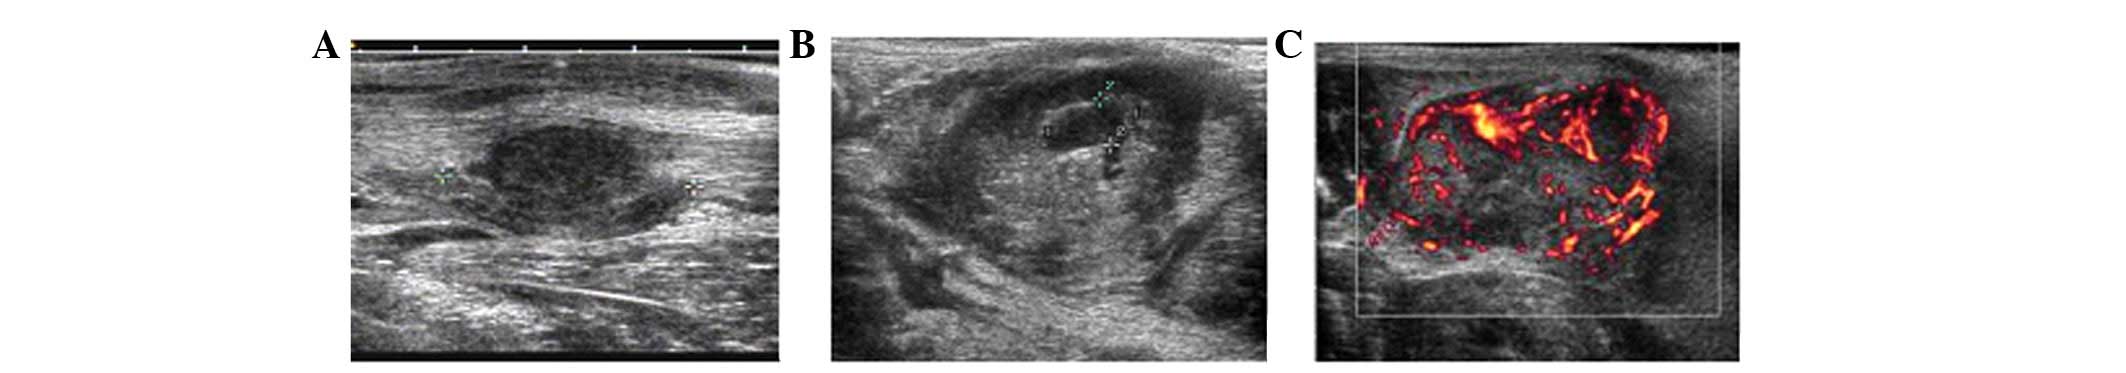

Contrast-enhanced ultrasonography of the rabbit VX2 tumor model: Analysis of vascular pathology

The accuracy of diagnosing tumors may be improved significantly by detecting the microvascular distribution. Indeed, contrast-enhanced ultrasonography (CEUS) has shown a distinct advantage in detecting microvasculature. This study aimed to determine the angiogenic characteristics of VX2 tumors in rabbits using CEUS. A total of 17 rabbits were injected with 0.5 ml VX2 cell suspension into the muscles of both hind legs to prepare the VX2 tumor models. At 14, 21, 28 and 35 days after tumor inoculation, CEUS was performed on the rabbits with 0.3 ml SonoVue following a local anesthesia. The pathological findings of the tumors were compared. A total of 12 rabbits survived after being inoculated with the tumor cells and developed a total of 38 tumors. The size of the tumors ranged from 1.12 to 10.85 cm. Using CEUS, all tumors demonstrated rim enhancement with some unenhanced regions. Enhancement began from the peripheral region and quickly showed internal reticular vessels. Regardless of the tumor size or the presence of necrosis, no complete enhancement of the tumors was observed. On microscopic examination, VX2 tumor cells were detected in striated muscles, immature blood capillaries and fibrosis tissues scattered in tumor nests. Immunohistochemical examination revealed that CD34+ cells appeared mainly in the muscles adjacent to vessels. In conclusion, CEUS may be an efficient method to evaluate angiogenesis and blood perfusion in VX2 tumors.